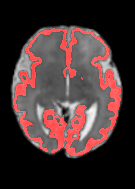

Fetal cortical plate segmentation is essential in quantitative analysis of fetal brain maturation and cortical folding. Manual segmentation of the cortical plate, or manual refinement of automatic segmentations is tedious and time-consuming. Automatic segmentation of the cortical plate, on the other hand, is challenged by the relatively low resolution of the reconstructed fetal brain MRI scans compared to the thin structure of the cortical plate, partial voluming, and the wide range of variations in the morphology of the cortical plate as the brain matures during gestation. To reduce the burden of manual refinement of segmentations, we have developed a new and powerful deep learning segmentation method. Our method exploits new deep attentive modules with mixed kernel convolutions within a fully convolutional neural network architecture that utilizes deep supervision and residual connections. We evaluated our method quantitatively based on several performance measures and expert evaluations. Results show that our method outperforms several state-of-the-art deep models for segmentation, as well as a state-of-the-art multi-atlas segmentation technique. We achieved average Dice similarity coefficient of 0.87, average Hausdorff distance of 0.96 mm, and average symmetric surface difference of 0.28 mm on reconstructed fetal brain MRI scans of fetuses scanned in the gestational age range of 16 to 39 weeks. With a computation time of less than 1 minute per fetal brain, our method can facilitate and accelerate large-scale studies on normal and altered fetal brain cortical maturation and folding.